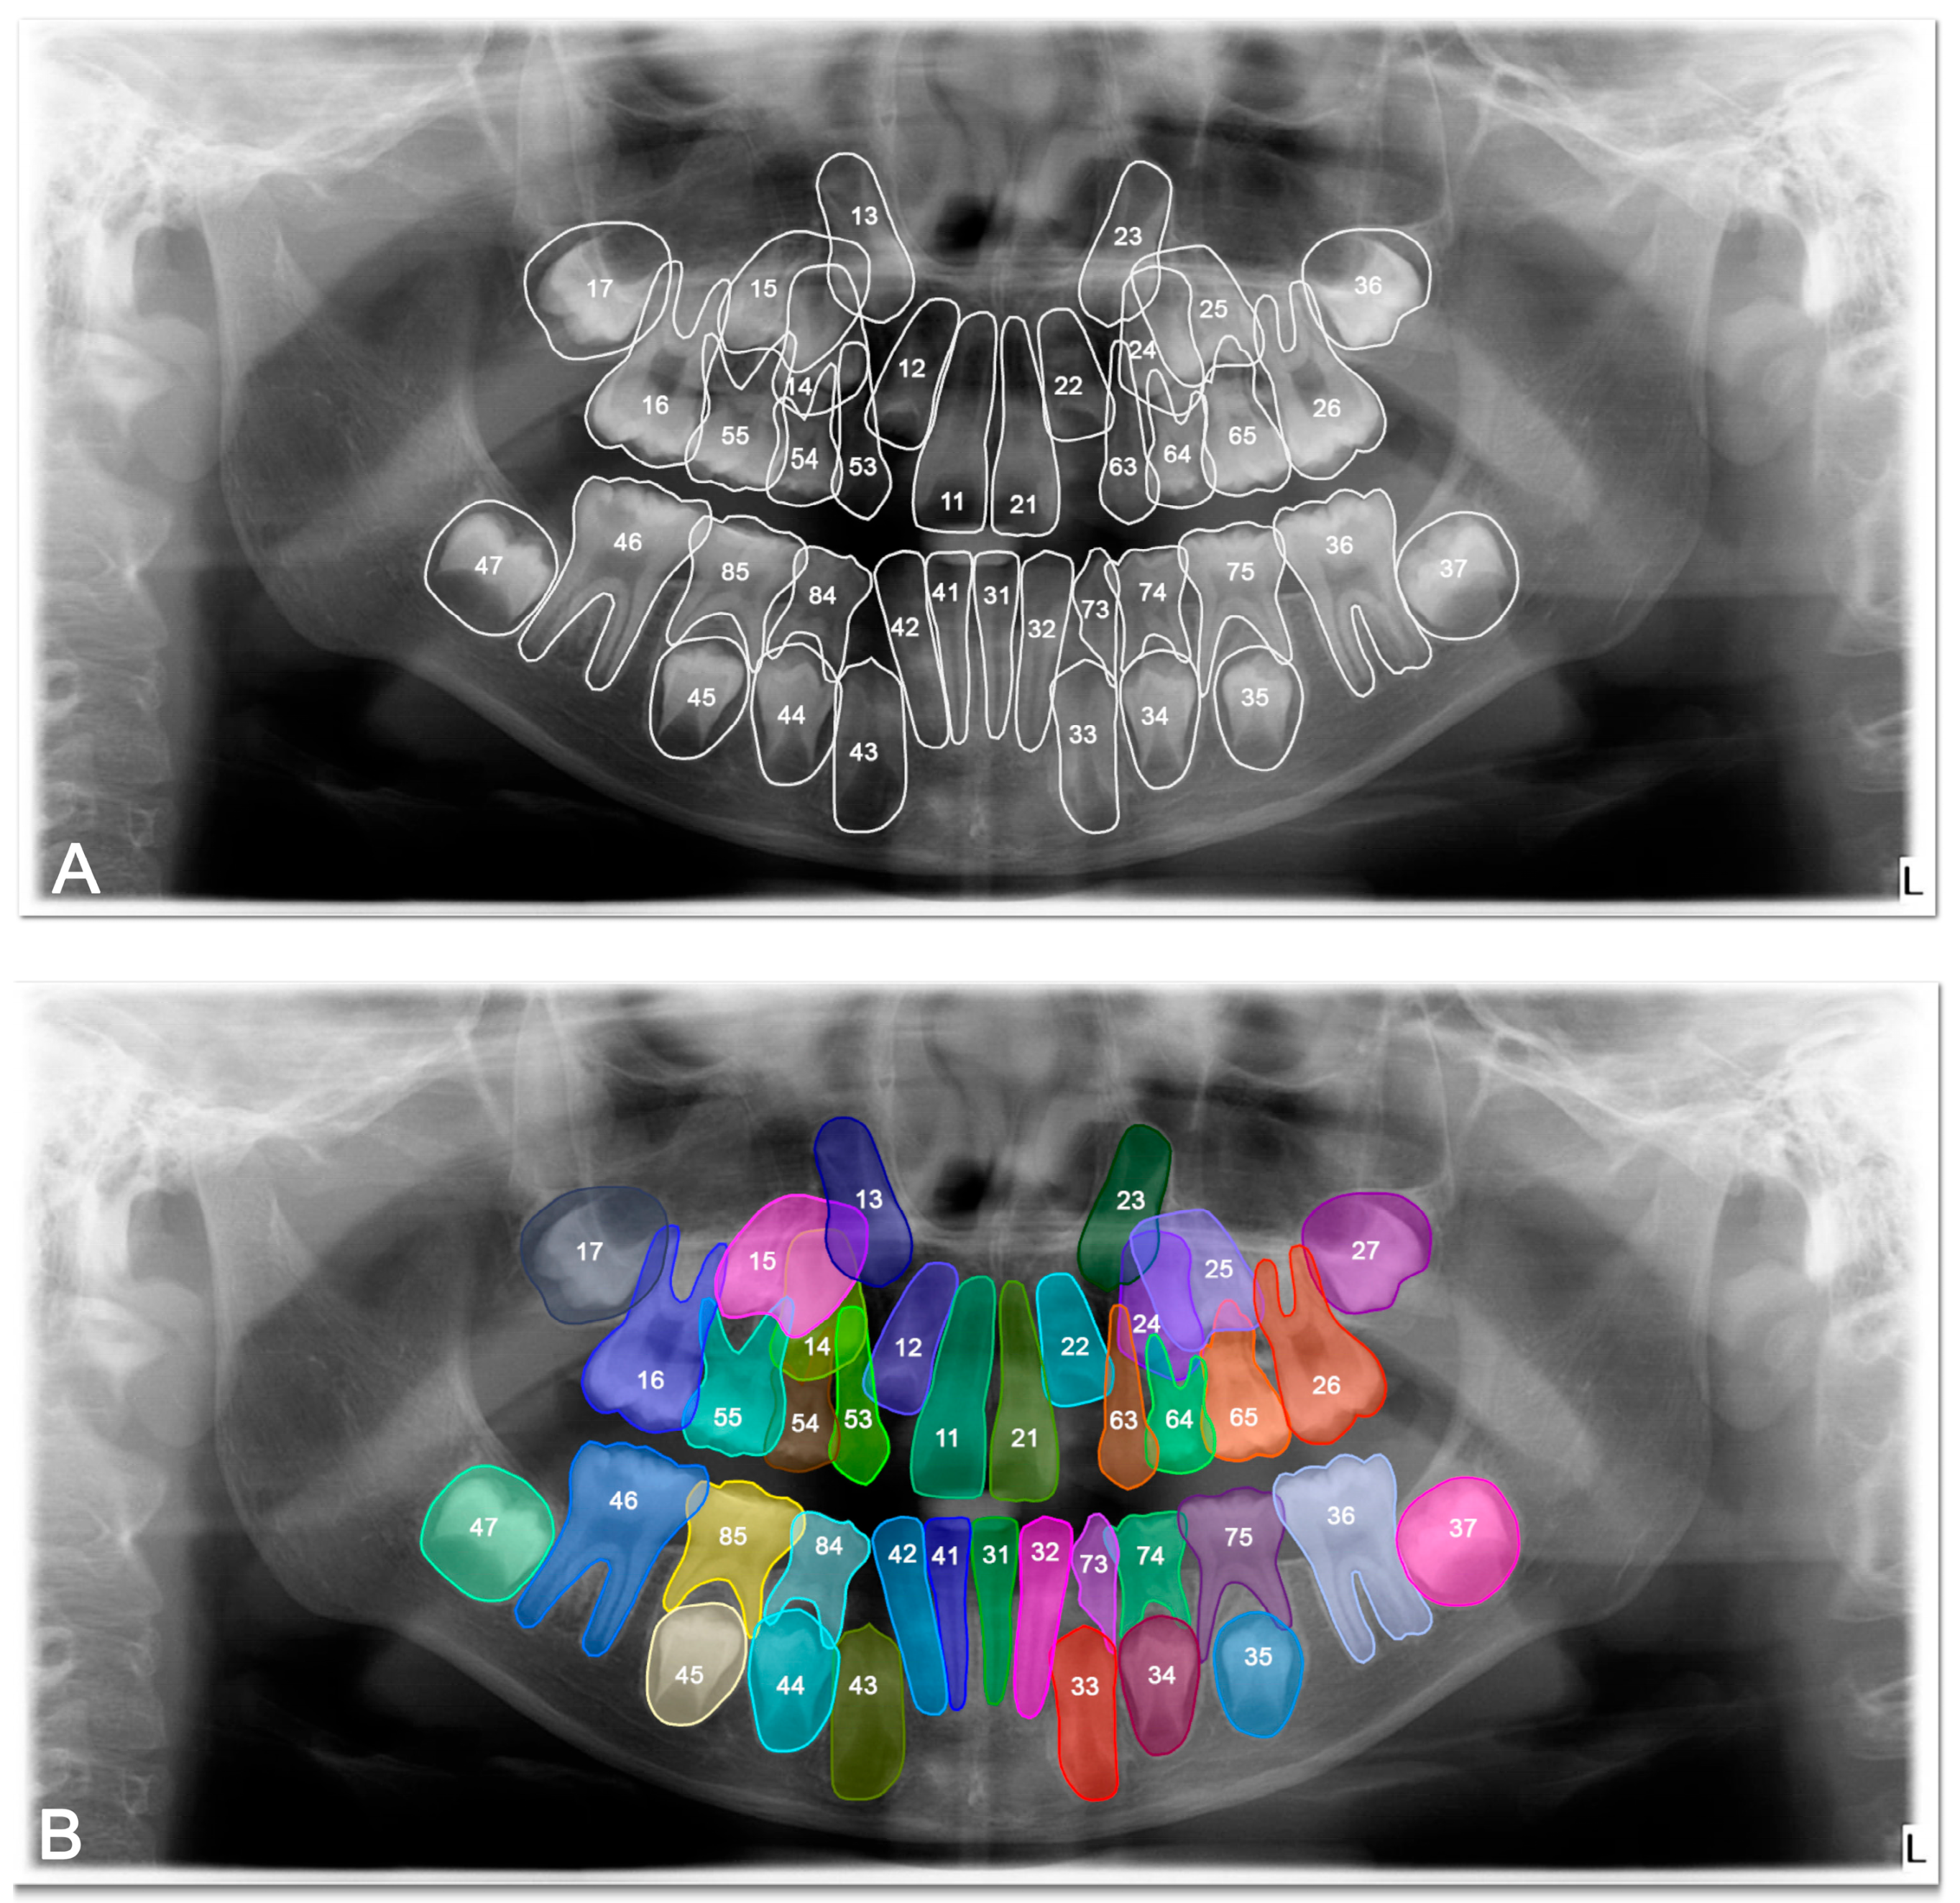

In the test phase, the U-Net-based deep learning model demonstrated robust segmentation and classification performance of primary and permanent teeth in panoramic radiographs. The Dice similarity coefficient (DSC) was 0.8773, indicating a substantial overlap between the model’s predicted segmentations and the ground-truth annotations (Figure 2 and Figure 3). Concurrently, the intersection over union (IoU) score of 0.8125 reflected the model’s ability to precisely localize target structures. Further supporting its robustness, the model achieved a precision of 0.9115 and a recall of 0.8974, leading to an F1 score of 0.9027. Collectively, these metrics confirm the model’s capacity to accurately delineate teeth while maintaining a balanced trade-off between false positives and false negatives. During the validation phase, the model maintained a high accuracy of 96.71%, indicating consistent performance across a variety of panoramic radiographs. Although the validation DSC (0.8062) and IoU (0.6936) were slightly lower than the test phase metrics—possibly due to dataset variability—the values remained indicative of reliable segmentation. Additionally, the validation loss was recorded at 0.2571, which falls within an acceptable error range for this type of segmentation task. Notably, the peak validation DSC reached 0.8540, while the highest IoU was 0.7556, suggesting that the model shows potential for further refinement.

Figure 3. Example images demonstrating the performance for segmentation of mixed dentition on panoramic radiographs between manual annotation by researchers and U-Net based artificial intelligence (AI)-predicted label masks. (A) Manual segmentation performed by clinicians. (B) Automatic segmentation by the model. In the segmentation figures, each tooth is represented with a distinct colour to visually differentiate regions; however, the model treated all teeth as unified segmentation classes during training.